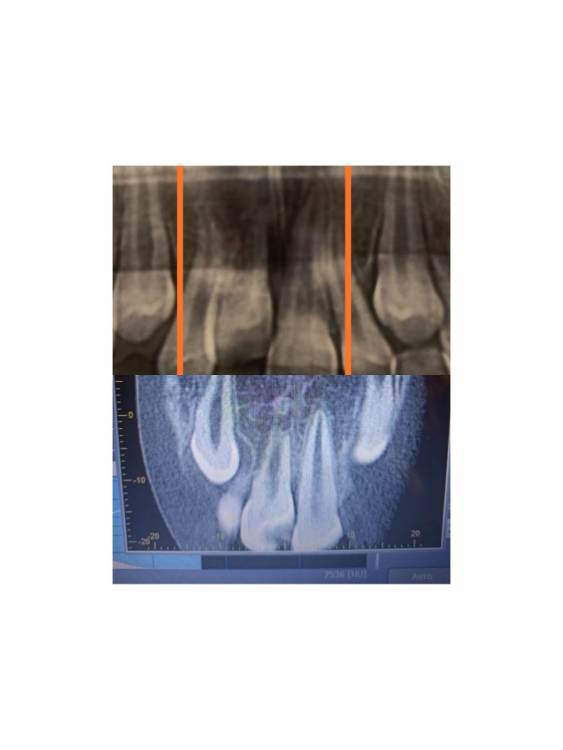

Pole4ka Опубликовано 6 июля, 2021 Автор Поделиться Опубликовано 6 июля, 2021 @wladdX @wladdX @wladdX 04.07.2021 в 21:44, wladdX сказал: 04.07.2021 в 22:25, Pole4ka сказал: @wladdX 20 часов назад, wladdX сказал: Резорбция корня + вертикальное расположение = анкилоз. То что зуб был с несформированной верхушкой корня помогло ему простоять так долго после реплантации в растущей челюстной кости. Конечно, хорошо бы, чтоб зуб смог простоять до имплантации, но на мой взгляд это маловероятно. Очень жаль, что такой неутешительные прогноз. Нам бы конечно дотянуть до имплантации. Но ведь за год изменений между двумя снимками практически нет, даже внешне (на снимках) стало чуточку лучше. И зуб не изменил цвет и неподвижный. Или это вообще ни о чем не говорит? Спасибо! Вверху 2021 год - панорамный снимок, внизу 2020 - КТ Ссылка на комментарий

Pole4ka Опубликовано 4 июля, 2021 Автор Поделиться Опубликовано 4 июля, 2021 38 минут назад, wladdX сказал: Насколько могу судить по приложенным скринам, резорбция корня всё же есть. Судя по Вашему рассказу, проведённая коллегами работа была верной, результат весьма неплохой. Рассчитывать на длительное пребывание зуба 11 в челюсти не приходится. Когда-то его придётся удалить. Спасибо большое за Ваше мнение и отклик! Нам бы дотянуть до момента, когда можно будет ставить имплант. Честно говоря, особой разницы между прошлогодним снимком (нижним среди снимков) и панорамным не вижу, поэтому возникла надежда, что резорбция приостановлена. А анкелоза нет? Спасибо! @wladdX Спасибо!!! Ссылка на комментарий

wladdX Опубликовано 5 июля, 2021 Поделиться Опубликовано 5 июля, 2021 Резорбция корня + вертикальное расположение = анкилоз. То что зуб был с несформированной верхушкой корня помогло ему простоять так долго после реплантации в растущей челюстной кости. Конечно, хорошо бы, чтоб зуб смог простоять до имплантации, но на мой взгляд это маловероятно. 1 1 Ссылка на комментарий

wladdX Опубликовано 4 июля, 2021 Поделиться Опубликовано 4 июля, 2021 Насколько могу судить по приложенным скринам, резорбция корня всё же есть. Судя по Вашему рассказу, проведённая коллегами работа была верной, результат весьма неплохой. Рассчитывать на длительное пребывание зуба 11 в челюсти не приходится. Когда-то его придётся удалить. 1 1 Ссылка на комментарий